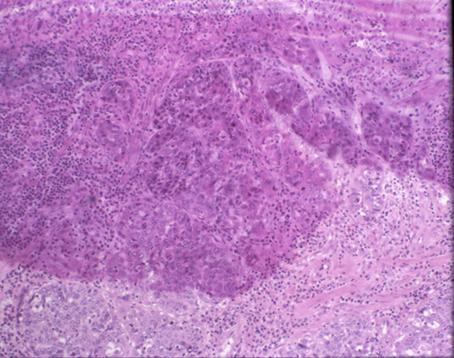

食道癌と胃癌を伴ったCronkhite-Canada症候群の病理組織像(ミクロ)  食道粘膜は肥厚し、全層に上皮の核異型を伴う配列の乱れが見られ扁平上皮癌の所見です。また、下方では粘膜下層への浸潤が認められます。全体に炎症性細胞浸潤も著明に見られます。

疾患(病理主体)の分類腫瘍様病変/Cronkhite-Canada症候群

部位(臓器別)食道/中

検査方法ミクロ

腫瘍の肉眼分類0型(表在型)/IIc型(IIc)

病変の最大径(ミリ)10〜14

腫瘍の深達度sm